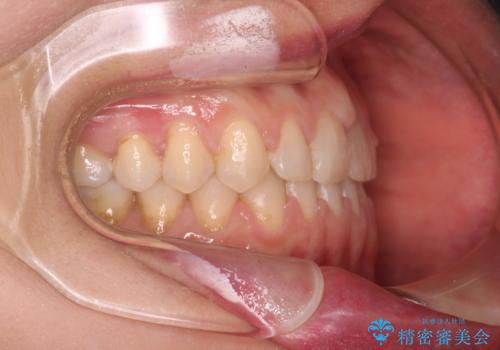

【審美装置】すきっ歯をワイヤー装置で治したい

- 前歯のすきっ歯が気になるということで来院されました。今回は抜歯はしないためワイヤー矯正かインビザライン矯正のどちらでも治療可能でしたが、患者さまのご希望により表のワイヤー装置にて治療をおこないました。

前歯に隙間がいくつかあったため、今回は上下でゴムかけを行いスペースを埋めるための力をかけて閉じました。もう少し早く終了する予定でしたが、ブラッシング不良による歯肉腫脹があり、一部スペースクローズに時間がかかりました。